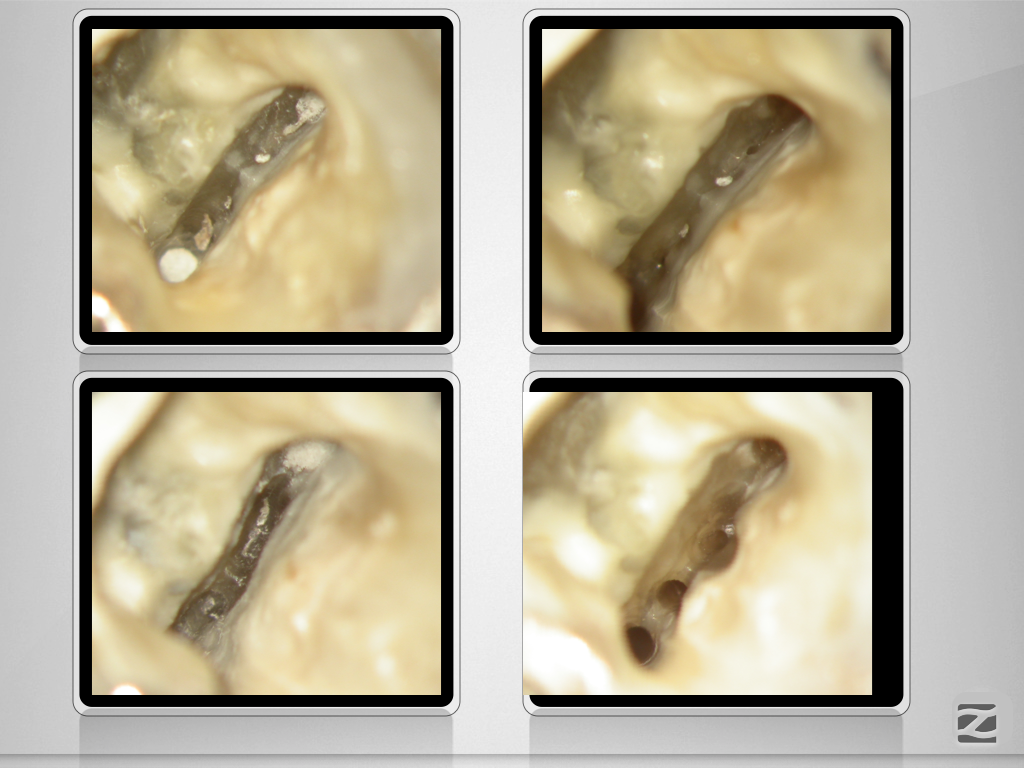

36D.005

7 auf einen Streich